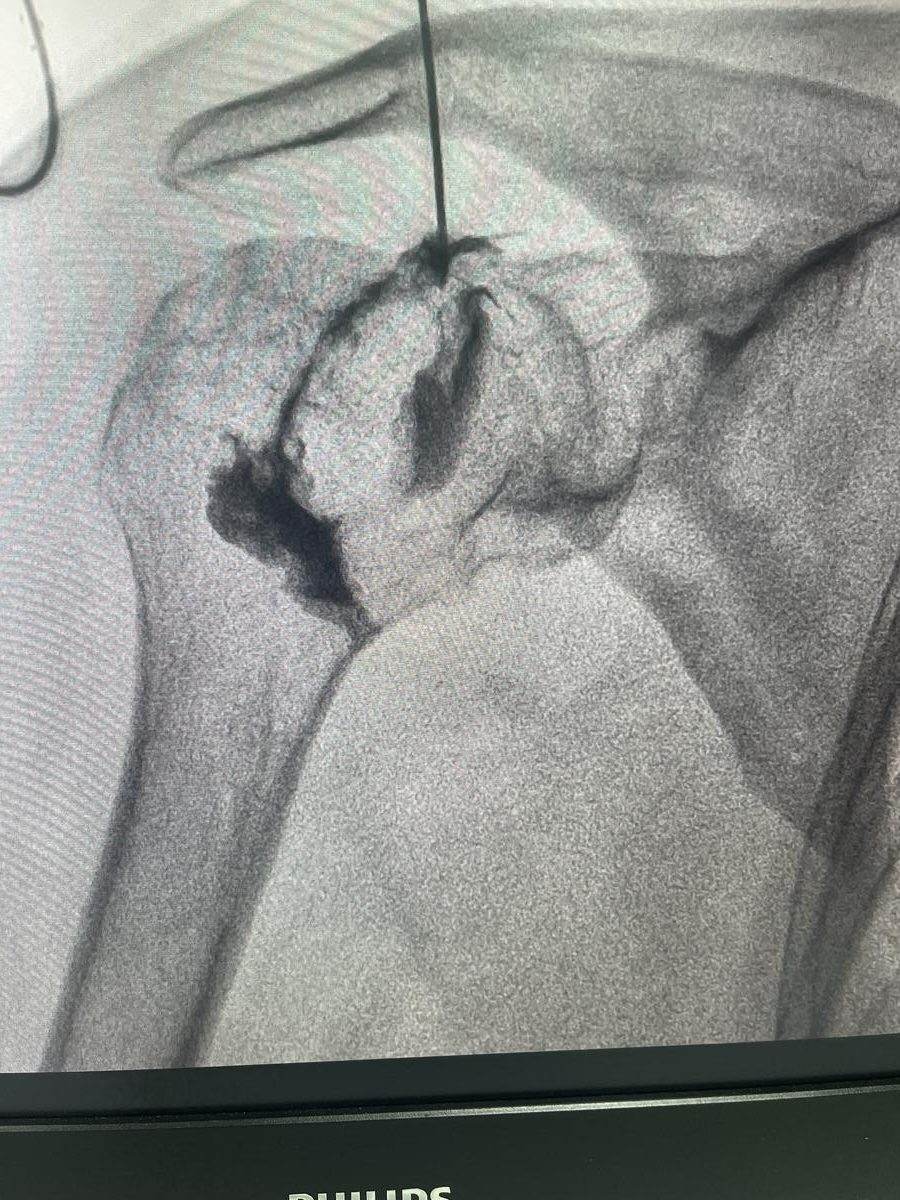

• Hydrodilatation for frozen shoulder, guided capsule expansion to restore movement

Hydrodilatation is an image-guided procedure where a mixture of saline, local anaesthetic, and corticosteroid is injected into the shoulder joint under pressure. This expands the contracted capsule, reduces inflammation, and helps restore range of motion. It is most effective during the freezing and frozen stages of adhesive capsulitis.